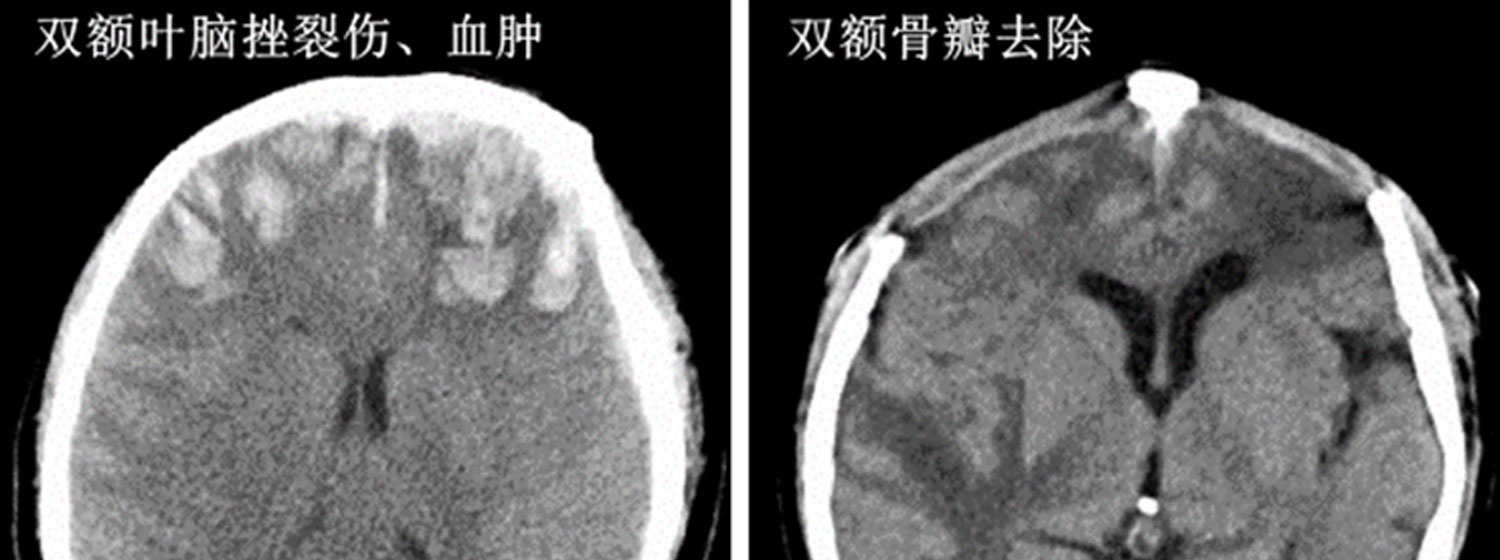

车祸时间:2022年2月26日约7时10分,骑电瓶车与小轿车相撞……